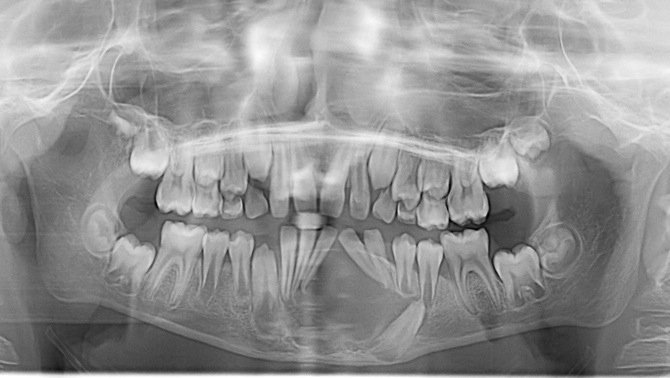

A imagiologia médica usada na medicina dentária, deve ser encarada como um meio de diagnóstico importante na abordagem de diferentes patologias, contribuindo muitas vezes de forma decisiva para o sucesso ou insucesso do tratamento.

O conhecimento das diferentes modalidades Imagiológicas de diagnóstico, impõe aos profissionais médicos, noções básicas e conhecimentos simples, que lhes permitam o manuseio destas diferentes modalidades na abordagem a diferentes patologias, tendo como princípio, regras simples e standardizadas de qualidade.

Pretende-se demonstrar um conjunto de medidas que lhes permitam evitar erros de execução, interpretação e definir que caminho seguir no objetivo da excelência na imagiologia médica utilizada na medicina dentária.

Falaremos dos exames mais utilizados na prática clínica diária e versaremos outras modalidades mais diferenciadas.